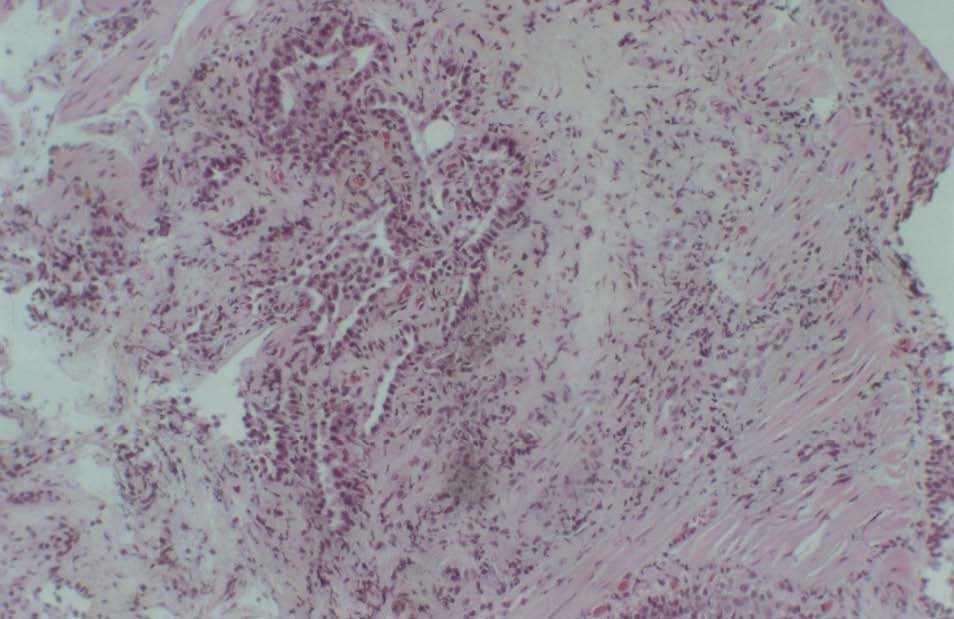

Al ingresar, la temperatura era de 36 °C, no presentaba adenopatías y en la exploración pulmonar mostraba crepitantes difusos. No se detectaron esplenomegalia, hepatomegalia ni masas abdominales. El examen neurológico, con la excepción de debilidad difusa, era normal. El recuento de leucocitos era de 2.600/μl con un 73% de células polimorfonucleares, un 10% de linfocitos y un 17% monocitos. La carga viral de 314.000 copias y la cifra de linfocitos CD4 de 80/μl. El hematocrito era del 34% y las plaquetas de 110.000/μl. Los valores de química hemática eran normales, excepto los valores de aspartatoaminotransferasa (82 U/l), gammaglutamiltranspeptidasa (193 U/l) y sodio (127 mEq/l). La gasometría arterial (fracción inspiratoria de oxígeno de 0,21) mostraba una presión arterial de oxígeno de 58,5 mmHg, pH de 7,36 y presión arterial de anhídrido carbónico de 24,4 mmHg. La radiografía de tórax era normal y la tomografía axial computarizada de alta resolución (TACAR) reveló la existencia de múltiples nódulos centrilobulares bien circunscritos, opacidades lineales en brotes de árbol (patrón tree in bud) y un área localizada de atrapamiento aéreo en el lóbulo inferior derecho en el escáner en espiración (figs. 1 y 2). El análisis de esputos fue negativo para bacilos ácido-alcohol resistentes pero se detectó Mycobacterium tuberculosis en la reacción en cadena de la polimerasa. Se inició tratamiento con isoniacida (300 mg/día), rifampicina (600 mg/día) y pirazinamida (1.500 mg/día) sin cambios clínicos ni radiológicos. La fibrobroncoscopia no mostró hallazgos significativos. El broncoaspirado y el lavado broncoalveolar fueron negativos para bacilos ácido-alcohol resistentes, así como el posterior cultivo de Löweinsten a los 60 días, pero la reacción en cadena de la polimerasa de M. tuberculosis fue positiva. En el análisis del lavado broncoalveolar se objetivó: un 33% de macrófagos alveolares, un 2% de linfocitos y un 65% de neutrófilos. La biopsia transbronquial reveló un ABA (fig. 3) e histiocitos de la submucosa bronquial que contenían amastigotes intracitoplásmicos de Leishmania (fig. 4). Se comenzó tratamiento con anfotericina liposomial pero el paciente falleció un mes después. La familia rehusó la realización de una autopsia.

Fig. 3. Biopsia transbronquial: adenoma bronquioloalveolar (lesiones endobronquiales con proliferación de células epiteliales columnares sin atipia nuclear).

Fig. 4. Biopsia transbronquial: histiocitos de la submucosa bronquial que contienen amastigotes de Leishmania intracitoplásmicos.

La descripción anatomopatológica del ABA se caracteriza por la proliferación de células redondas a lo largo de las paredes alveolares con un grado de atipia nuclear variable. La mayoría de estos hallazgos se ha asociado al cáncer de pulmón o a la neumonitis intersticial3. Muchas publicaciones han señalado que estas lesiones pueden corresponder a fases premalignas tempranas de una neoplasia glandular con una potencial evolución a carcinoma4. El ABA se ha descubierto de forma casual en el examen microscópico de muestras quirúrgicas pulmonares resecadas de pacientes en quienes previamente no se había detectado mediante estudios radiológicos de tórax. En la TACAR el ABA aparece como nódulos pulmonares pequeños y bien circunscritos con atenuación en "vidrio deslustrado"5.

En el presente caso se imbrican 2 procesos patológicos diferentes: por un lado, la infestación pulmonar por Leishmania, secundaria a una inmunodeficiencia adquirida por infección por el virus de la inmunodeficiencia humana, que puede ser el origen de una bronquiolitis obliterante, y por otro lado, el ABA, que agravó el problema respiratorio del paciente. El ABA es un posible precursor del carcinoma bronquioalveolar, que pudiera haberse desarrollado posteriormente sobre las lesiones inflamatorias preexistentes. Aunque en principio no se ha demostrado que el ABA tenga relación con ninguna infección respiratoria, la hipotética asociación entre infección por Leishmania y ABA no se puede descartar al ser desconocido el origen del ABA y haberse presentado de forma sincrónica en nuestro paciente.